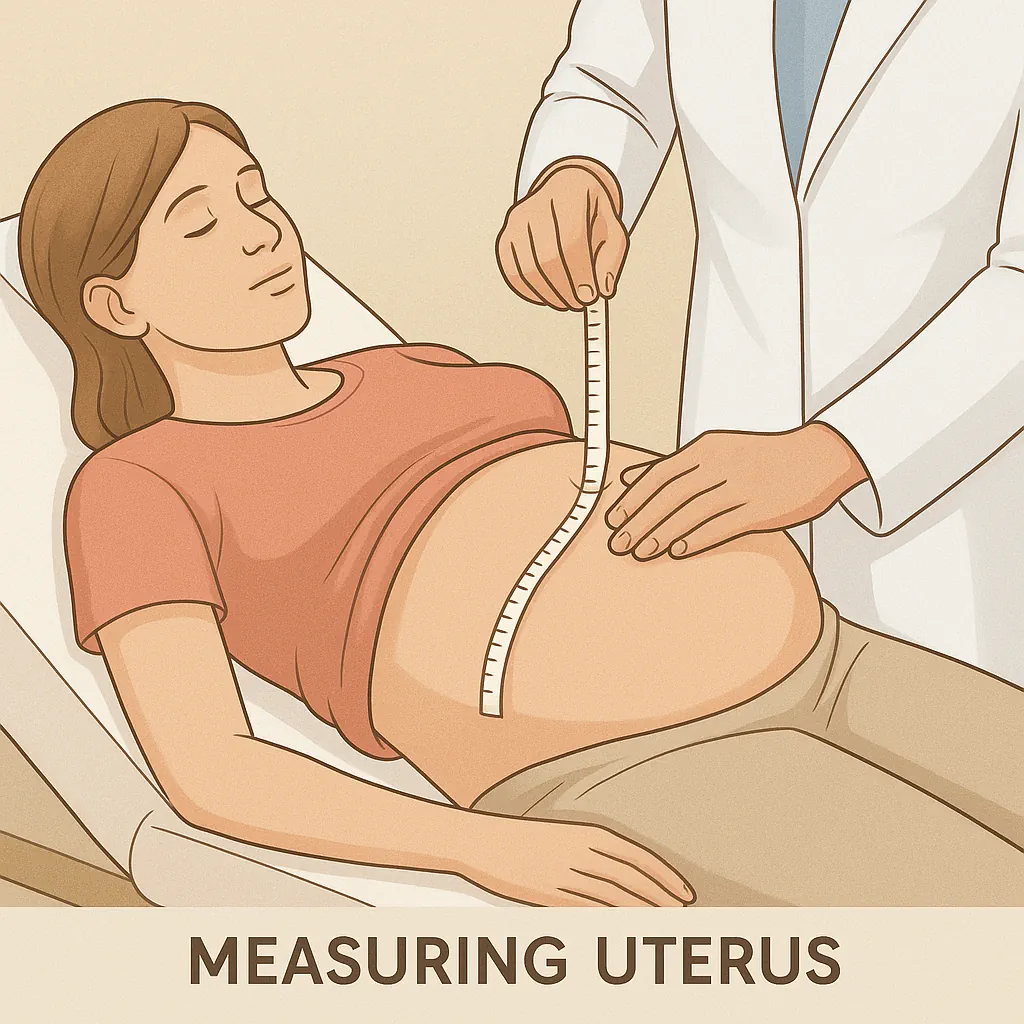

🔹 Uterine Growth and Belly Expansion

Your uterus is now about the size of a grapefruit, positioned roughly an inch (2.5 cm) below your navel. You may notice your belly becoming slightly more prominent — the first visible sign of pregnancy for many mothers.

When lying on your back, you may be able to feel the top of your uterus by gently pressing just below your belly button. Don’t worry — touching your abdomen won’t harm your baby. The amniotic sac and the strong uterine wall provide excellent protection.

At each prenatal visit, your obstetrician will measure the fundal height (from the pubic bone to the top of the uterus) to ensure that the baby’s growth matches the expected timeline.

💡 By week 16, your uterus should reach halfway between the pubic bone and the navel — a reassuring sign of normal development.